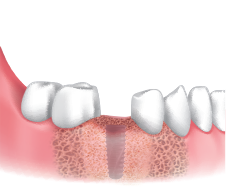

Secuencia de obtención :

Obtención de hueso vestibular utilizando fresa de recolección

Ø3.5 / 4.0 / 4.5 / 5.0 / 6.0.

Seleccionar la fresa de acuerdo al diámetro e indicaciones clínicas.

Fresar entre 300 a 500 RPMcon irrigación y obtenga limallas de hueso autólogo.

Aplicar el hueso obtenido en el sitio de regeneración.